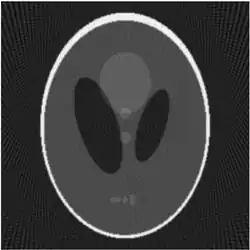

If a function represents an unknown density, then the Radon transform represents the projection data obtained as the output of a tomographic scan. The inverse of the Radon transform can be used to reconstruct the original density from the projection data, and thus it forms the mathematical underpinning for tomographic reconstruction, also known as iterative reconstruction.

The Radon transform data is often called a sinogram because the Radon transform of an off-center point source is a sinusoid. Consequently, the Radon transform of a number of small objects appears graphically as a number of blurred sine waves with different amplitudes and phases.

Explicit and computationally efficient inversion formulas for the Radon transform and its dual are available. The Radon transform in dimensions can be inverted by the formula:[11] where , and the power of the Laplacian is defined as a pseudo-differential operator if necessary by the Fourier transform: For computational purposes, the power of the Laplacian is commuted with the dual transform to give:[12] where is the Hilbert transform with respect to the s variable. In two dimensions, the operator appears in image processing as a ramp filter.[13] One can prove directly from the Fourier slice theorem and change of variables for integration that for a compactly supported continuous function of two variables: Thus in an image processing context the original image can be recovered from the 'sinogram' data by applying a ramp filter (in the variable) and then back-projecting. As the filtering step can be performed efficiently (for example using digital signal processing techniques) and the back projection step is simply an accumulation of values in the pixels of the image, this results in a highly efficient, and hence widely used, algorithm.